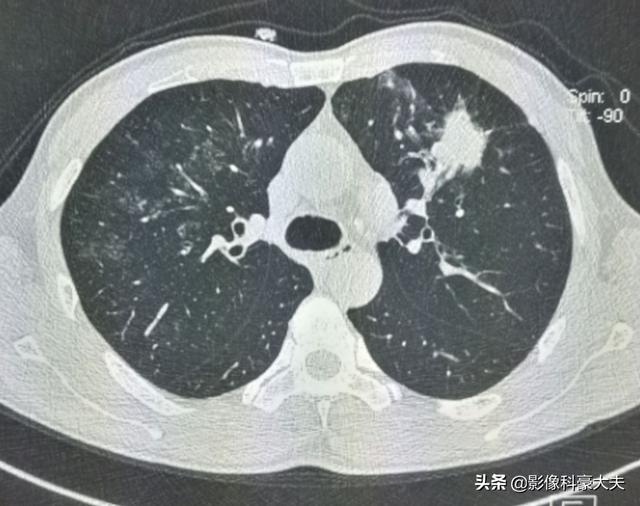

咳と発熱があり、気管支肺炎と左肺がんの両方が見つかった44歳の男性の例を見てみよう:

肺炎は抗生物質で治り、その後、左肺がんの摘出手術。手術から2年半後、右肺に転移が見つかった: